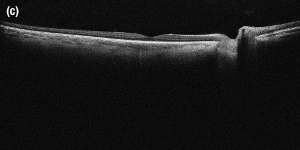

An Image of the Anterior of the Eye Taken with the SLD830S-A10 in a Modified Ganymede System

それぞれの画像の組織内深度は6.2 mmで、36 kHzのA-スキャンレートで撮影されています。